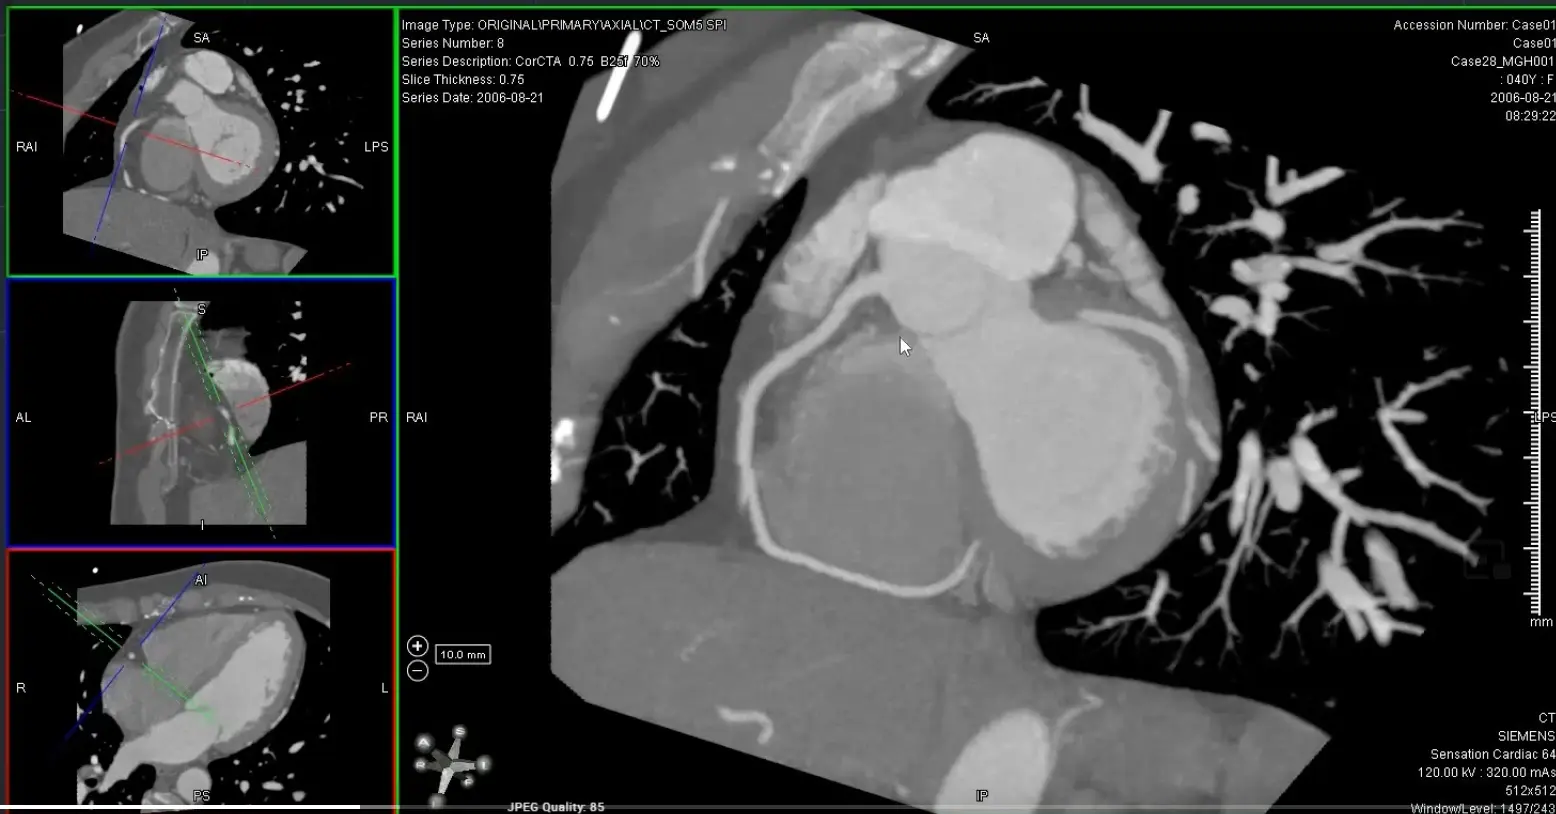

- Coronal view: Position crosshair (⌖) at mid-RCA

- Axial view: center on the SAX view of the RCA

- rotate ⌖ in the axial view until you are aligned parallel to the ventricular septum on your coronal window

- In your axial view, rotate ⌖ to align the orthogonal view (e.g. coronal window) so that the orthogonal view is along the atrioventricular groove

- Switch to MIP view

- MIP will help give you an overview of the vessel. Once you identify some areas of concern → switch to thin-slice images for closer investigation 🔍 and evaluation for stenosis.

MPR of ‘C’ view of RCA

Above, but changed to MIP